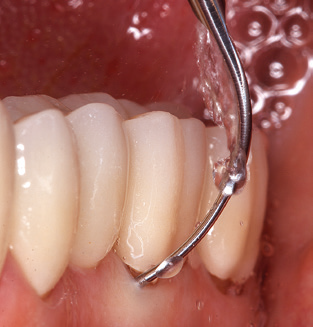

Updating the patient’s medical history is an important aspect of SPT and should occur at least once per year. It helps the dental team to identify and document any new risk factors. Especially when a patient is treated over many years, it is important to establish whether patient-specific and general health risk factors have changed. This primarily concerns a heightened risk as a result of diabetes, but other general conditions (cardiovascular disease and neoplasia) can also produce a modified risk profile as a result of the treatment performed and medication administered. Accordingly, updating the medical history as part of SPT is very important, as a modified risk profile may trigger the need to adapt the treatment interval. In the next step, it is important to afford the diagnostics due attention. Whilst instruments are a central aspect of SPT, findings and their documentation must never be neglected. The periodontological findings are essential for a good diagnosis; increases in the pocket depths and the BOP index are clear indicators of advancing periodontal and peri-implant disease. As such, the team should not shy away from probing implants too, with the aim of gathering the requisite data. At the same time, it is important to use periodontal probes with millimetre markings. Metallic probes have already been used for determining pocket depths around natural teeth for decades. In the case of implants, the challenge of recording correct and reproducible pockets depths is even greater. As the discrepancy between the implant diameter and the contour of the superstructure regularly results in overcontouring of the superstructure, flexible probes which still feature millimetre markings are a sensible solution for measuring pocket depths around implants (e.g., Colorvue Kit PCV11KIT6, Hu­Friedy; Fig. 4).

Fig. 4: Flexible probes with millimetre markings are recommended for the probing of dental implants (e.g. Colorvue Kit PCV11KIT6, Hu­Friedy). – Fig. 5a and b: A straight working tip (1P, W&H Dentalwerk Bürmoos GmbH) is a suitable instrument for use on all natural teeth. – Fig. 6: Curved working tips (3Pr/3Pl, W&H Dentalwerk Bürmoos GmbH) lend themselves to the processing of difficult-to-reach areas of the tooth and root surfaces (e.g. furcations). – Fig. 7: The tapered, hexagonal implant cleaning tip (1I, W&H Dentalwerk Bürmoos GmbH) permits atraumatic and efficient cleaning of the crown and abutment surfaces. – Fig. 8: Titanium and carbon curettes are suitable instruments for the manual cleaning of the implant surfaces.